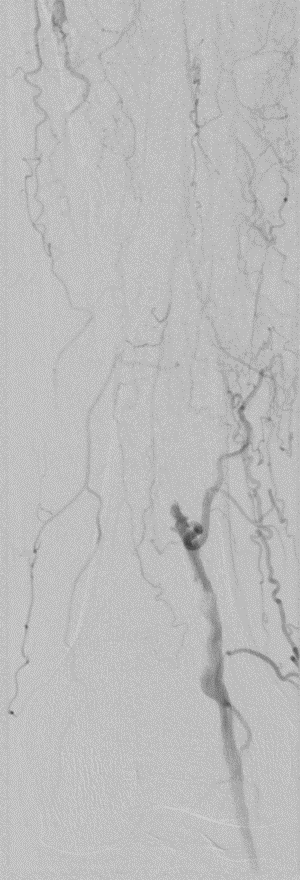

★ Case 1

noproximal stump in SFA,>250mm

★ Case 2

significantdistal collaterals